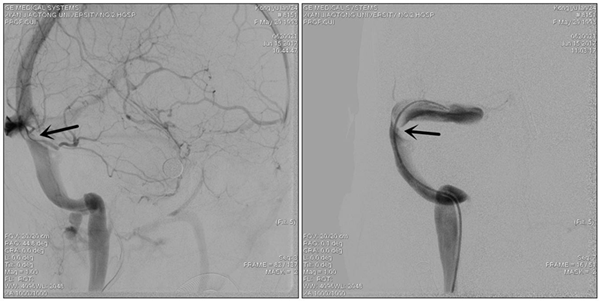

患者转入我科时头痛剧烈、烦躁不安、双眼视力仅有眼前指数,强力脱水的状态下颅内压仍大于600mmH2O。我们按压了分流阀,发现分流阀已经堵塞,家属急切的要求我们重新给她做分流手术,缓解颅内压。但崔刚、许刚二位医生仔细了解患者病史,认真研究患者的影响资料,考虑患者颅内高压、视力下降、癫痫发作这一系列症状是由于颅内静脉窦狭窄造成的,要想彻底解决这些问题的关键不是分流手术,而是恢复颅内静脉窦的正常回流。经与患者家属的充分沟通后,家属接受了我们的诊疗思路,次日为患者行全脑血管造影术,发现患者右侧横窦狭窄严重,经测量狭窄远近端压力差为310 mmH2O。根据国际指南,狭窄远近端压力差大于130 mmH2O就有实施静脉窦支架成形术的指征。为了进一步确定手术效果,崔刚、许刚二位医师先为患者实施了静脉窦狭窄球囊扩张术,球囊扩张后,患者诉头痛明显缓解、视力也开始恢复。次日腰穿显示颅内压已经降到了270mmH2O,患者及家属非常满意。

术前造影显示静脉窦狭窄